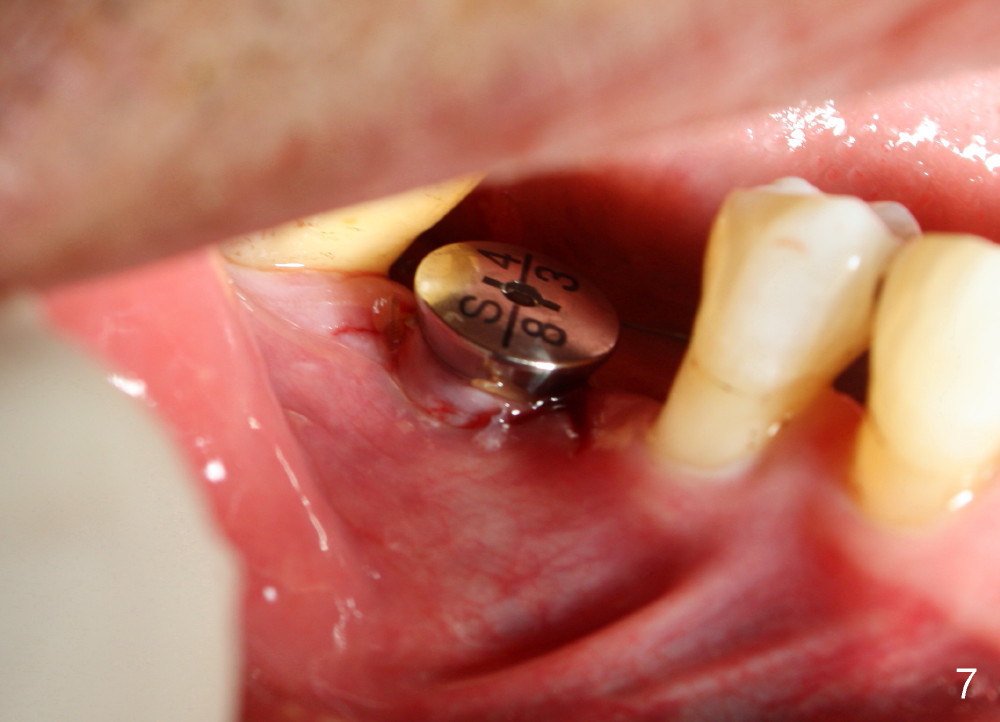

When a positioning pin is placed in the osteotomy with 10 mm deep, the sensor cannot be placed deep enough because of pin interference so no IAC is visible (Fig.4). When the pin is removed and the sensor is placed low enough, IAC is clearly shown, but the osteotomy is barely visible (Fig.5 pink dashed line). With information obtained from pre- (Fig.2,3) and intra- (Fig.4,5) op PA, twelve mm of osteotomy appears to be appropriate. A final implant (5.3x12 mm) is placed with separation from IAC (Fig.6, insertion torque 50 Ncm). A healing abutment is placed (Fig.7,8), which helps retain perio dressing (Fig.9). Two weeks later, the gingiva heals around the abutment (Fig.10). Four months postop, the implant appears to osteointegrate (Fig.11). A cemented abutment is placed (Fig.12). With supragingival margin, oral hygiene is easily maintained (Fig.13). Due to delayed placement, the gingival embrasure is extremely large (*). The issue is much less with immediate implant.